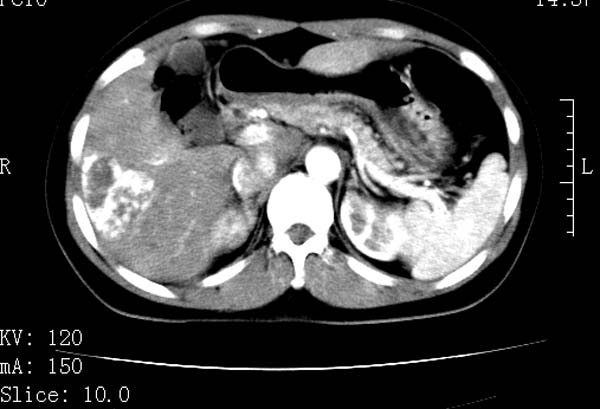

标题: CT22086:女44岁 肝右叶占位增强示巨大血管瘤,门脉期发现小 [打印本页]

标题: CT22086:女44岁 肝右叶占位增强示巨大血管瘤,门脉期发现小

支持肝右叶血管瘤诊断。 小病灶亦考虑血管瘤改变。温习一下:

肝海绵状血管瘤ct平扫常呈均匀低密度,与邻近血管密度相仿。在脂肪肝背景下可呈相对高密度。在增强扫描时,一般早期(动脉期)呈周边结节状或弧形强化,其密度与同层面的血管密度相仿,随着时间延迟向中央渐进性充填,注药后5~7分钟,逐渐扩大至全瘤强化,强化密度逐渐降至稍高于或等于正常肝脏。大的血管瘤往往中央有星形、大的低密度区,可以为纤维化或囊性变所致,纤维化成分可在延迟2 o分钟时完全充填,呈等密度,但囊变区则不会强化。不典型ct表现常见于≤3 cm的小血管瘤。小的血管瘤可以在动脉期即呈全部致密的均匀强化,不呈典型的周边结节状强化表现,但其密度往往较高,与主动脉相仿,在延迟期呈高或等密度。其他不典型的ct表现有:增强扫描强化不明显,呈点状较轻程度的强化,充填慢,可能与供血动脉较细和较大的血管间隙有关以及中央先强化等。

延迟扫描三个病灶都呈等密度改变。肝多发血管瘤,较典型。